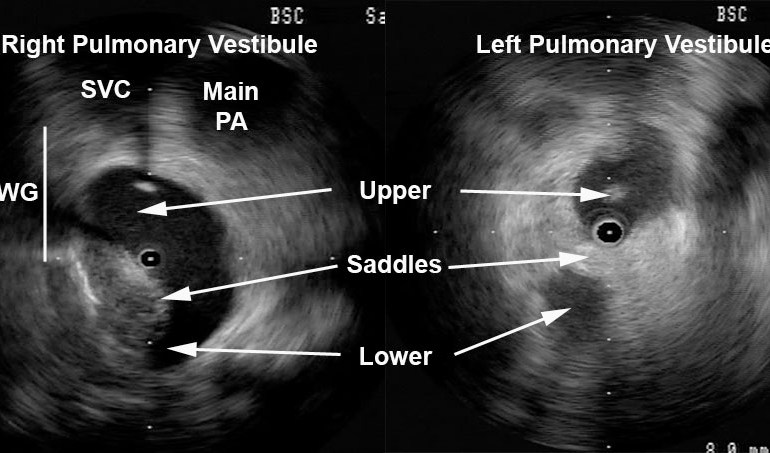

Detailed anatomy of the pulmonary veins can also aid in catheter positioning and stability as well as monitor for procedural complications (discussed later). Figure 3 provides views of the left and right pulmonary vestibules. The left upper (LUPV) and lower pulmonary veins (LLPV) are visualized as are the saddles. The right intervenous saddle is not as clearly differentiated as the left in this particular example to give the reader a better overall view of the structures surrounding the right pulmonary vestibule such as SVC, main PA, and Waterston’s groove (WG). Waterston’s groove is a fat-filled depression formed as the left and right atria fold into one another; Waterston’s groove is often dissected by surgeons to expose the left atrium. Radial ICE can be carefully placed within each individual pulmonary veins to guide catheter ablation as previously described. [1,2,3]

Figure 3  Radial ICE Anatomy of Left and Right Pulmonary Vestibules. The right pulmonary vestibule is shown with the early portions of the upper and lower pulmonary veins. Superior to the right pulmonary veins one can see the main pulmonary artery and superior vena cava. The approximate location of Waterston’s groove is depicted by the solid line.  A more distal view of the left pulmonary vestibule (compared to Figure 2) clearly differentiates the upper and lower PV’s as well as the intervenous saddle.